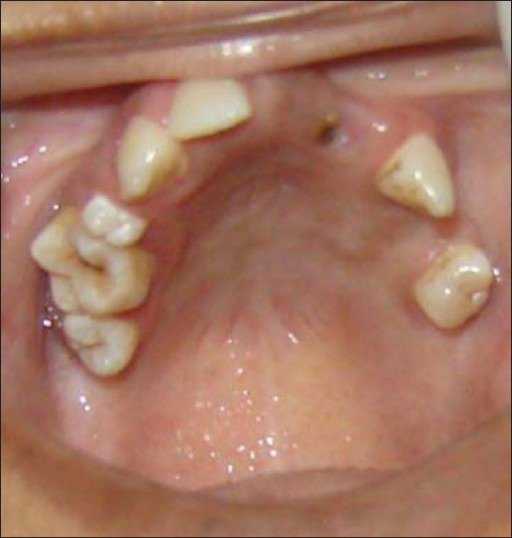

Hipodoncia*

Hypodontia*

Ausencia congénita de uno o más dientes.

A condition characterized by having fewer teeth than normal.